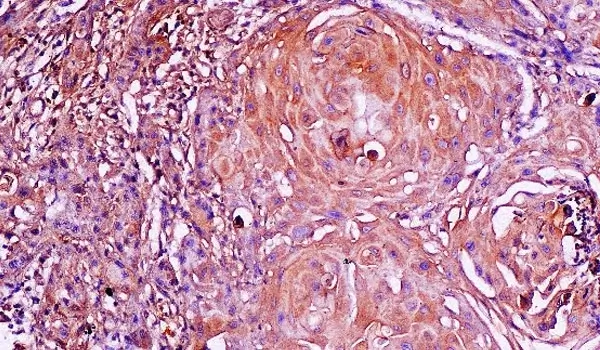

Immunohistochemistry

An immunohistochemistry (IHC) lab is a specialized laboratory dedicated to conducting experiments and analyses related to immunohistochemistry techniques. Immunohistochemistry is a powerful method used to detect specific proteins or antigens within tissue sections or cell samples using antibodies and staining processes. It is widely used in various fields of research, including biology, medicine, pathology, and oncology.

Immunohistochemistry Laboratory

The Immunohistochemistry laboratory offers a variety of services for antigen detection in tissues in the field of surgical pathology and research projects.